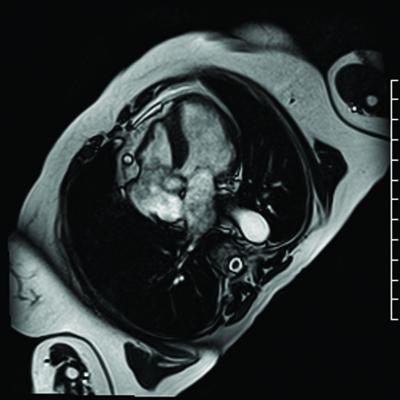

For the study, Kuetting and colleagues recruited 20 healthy radiologists, including 19 men and one woman, with a mean age of 31.6 years. Each of the study participants underwent cardiovascular magnetic resonance (CMR) imaging with strain analysis before and after a 24-hour shift with an average of three hours of sleep.

"Cardiac function in the context of sleep deprivation has not previously been investigated with CMR strain analysis, the most sensitive parameter of cardiac contractility," Kuetting said.

Following short-term sleep deprivation, the participants showed significant increases in mean peak systolic strain (pre = -21.9; post = -23.4), systolic (112.8; 118.5) and diastolic (62.9; 69.2) blood pressure and heart rate (63.0; 68.9). In addition, the participants had significant increases in levels of thyroid stimulating hormone (TSH), thyroid hormones FT3 and FT4, and cortisol, a hormone released by the body in response to stress.